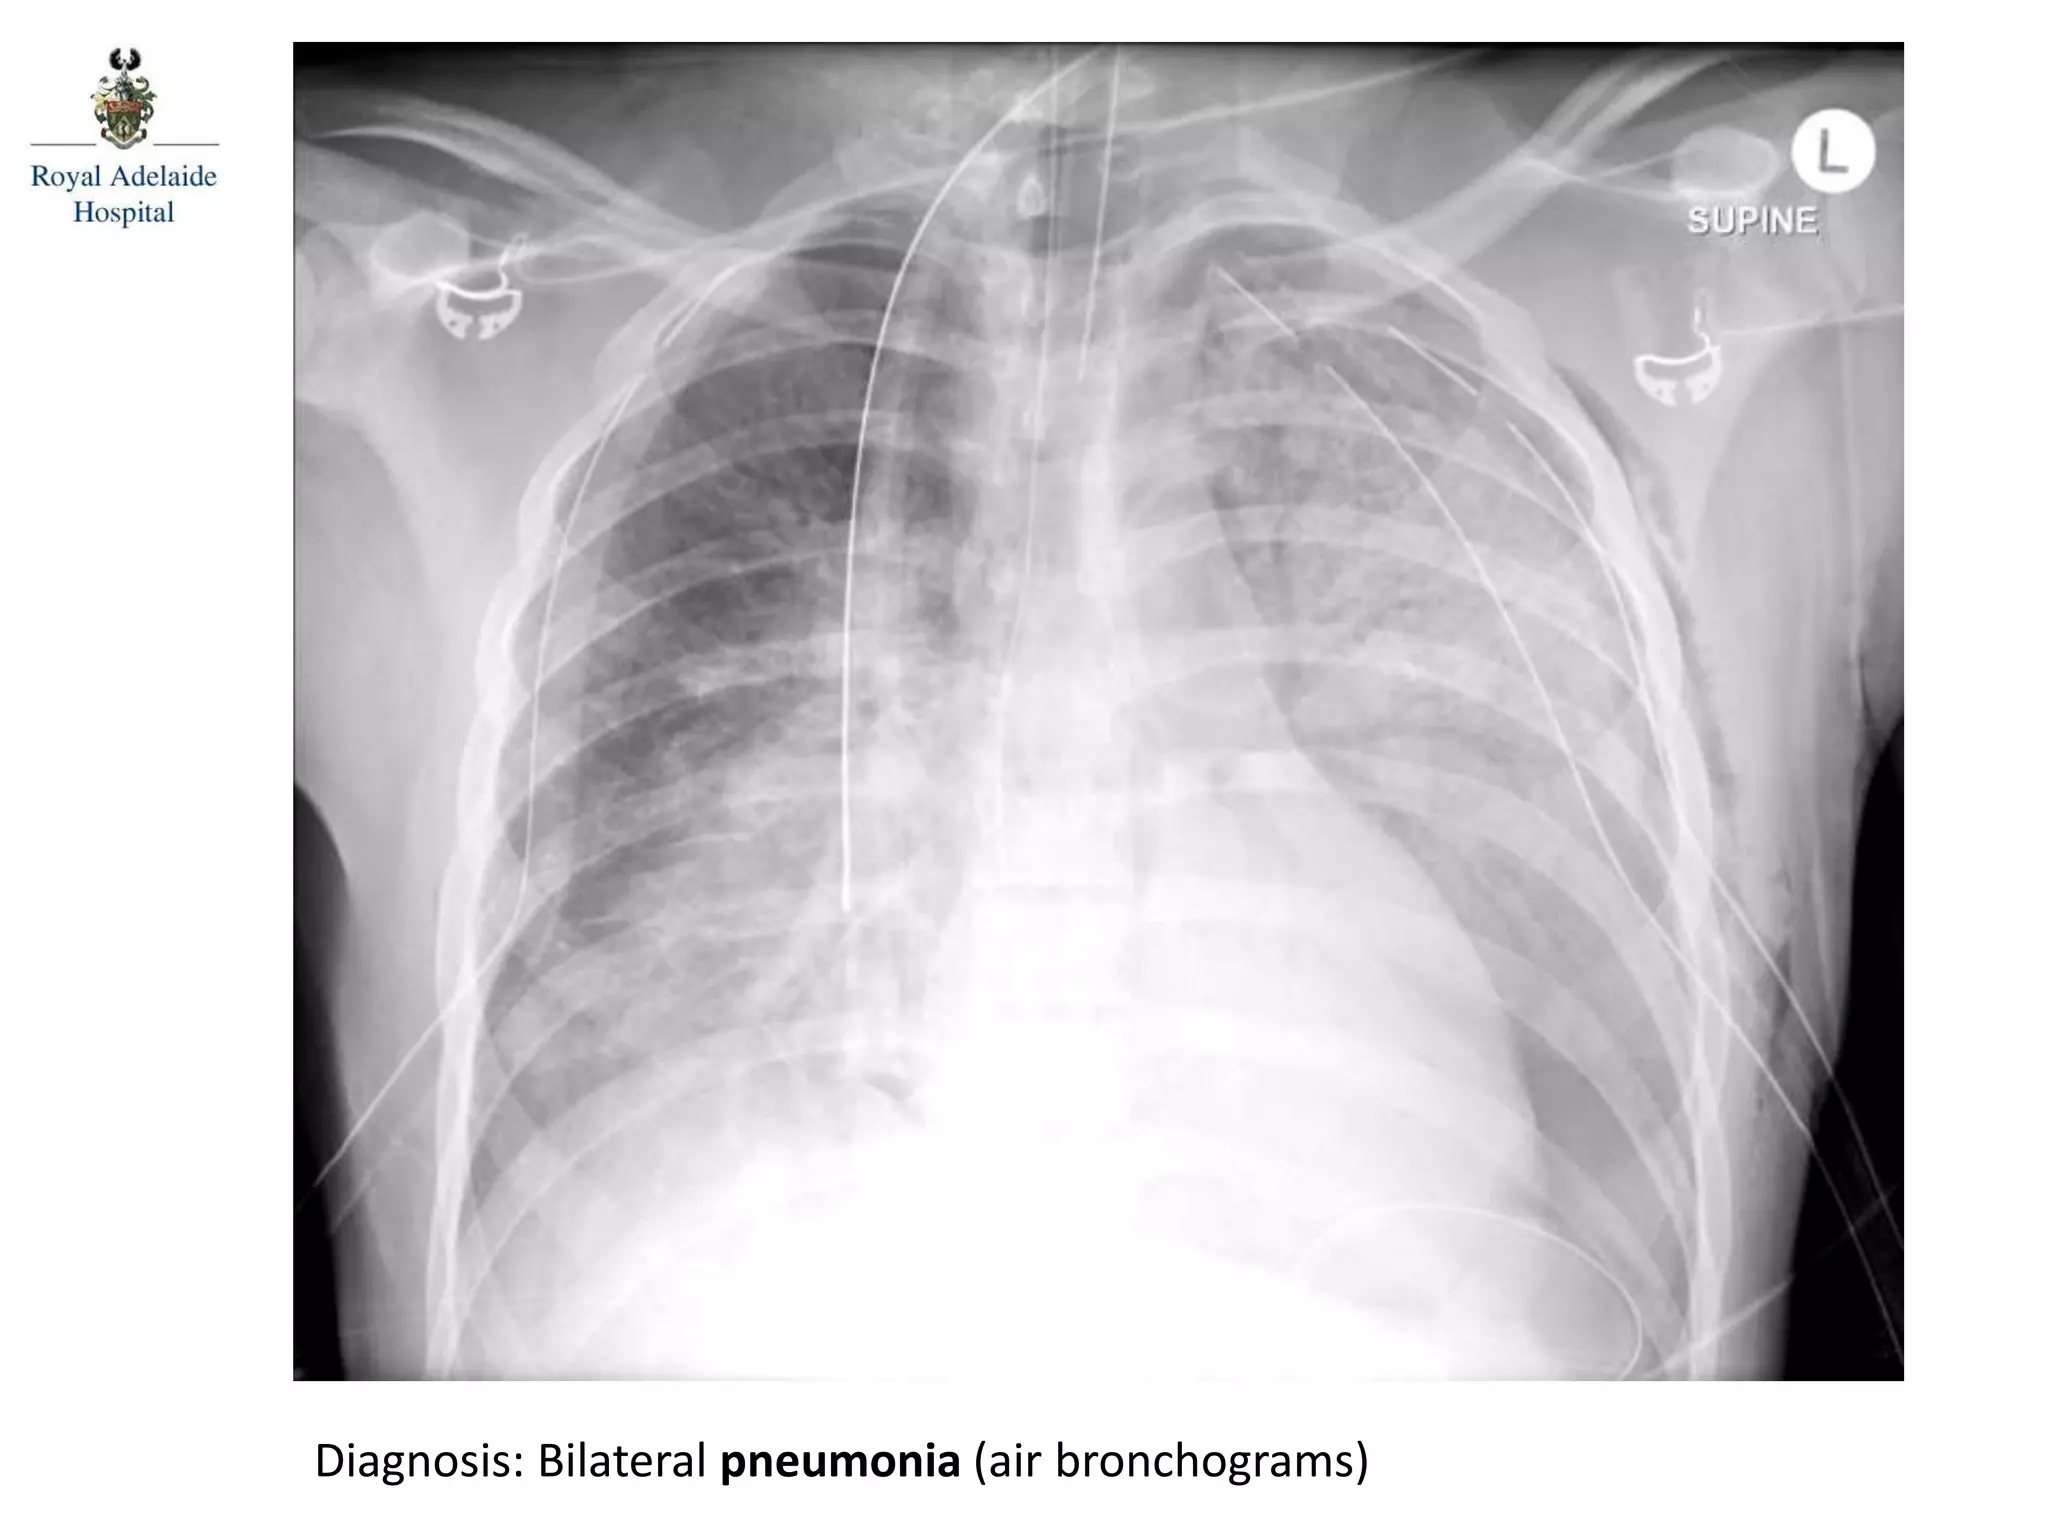

Diagnosis: Bilateral pneumonia (air bronchograms)